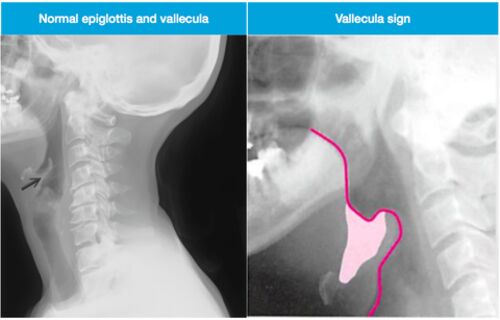

最新のNew England Journal Images of Cilinical Medicineです。 今回は急性喉頭蓋炎についてです。 https://www.nejm.org/doi/full/10.1056/NEJMicm1816761 48歳の男性で3日ほどの嚥下時痛や発熱、呼吸困難を主訴に来院し、Thumb signをきっかけに急性喉頭…